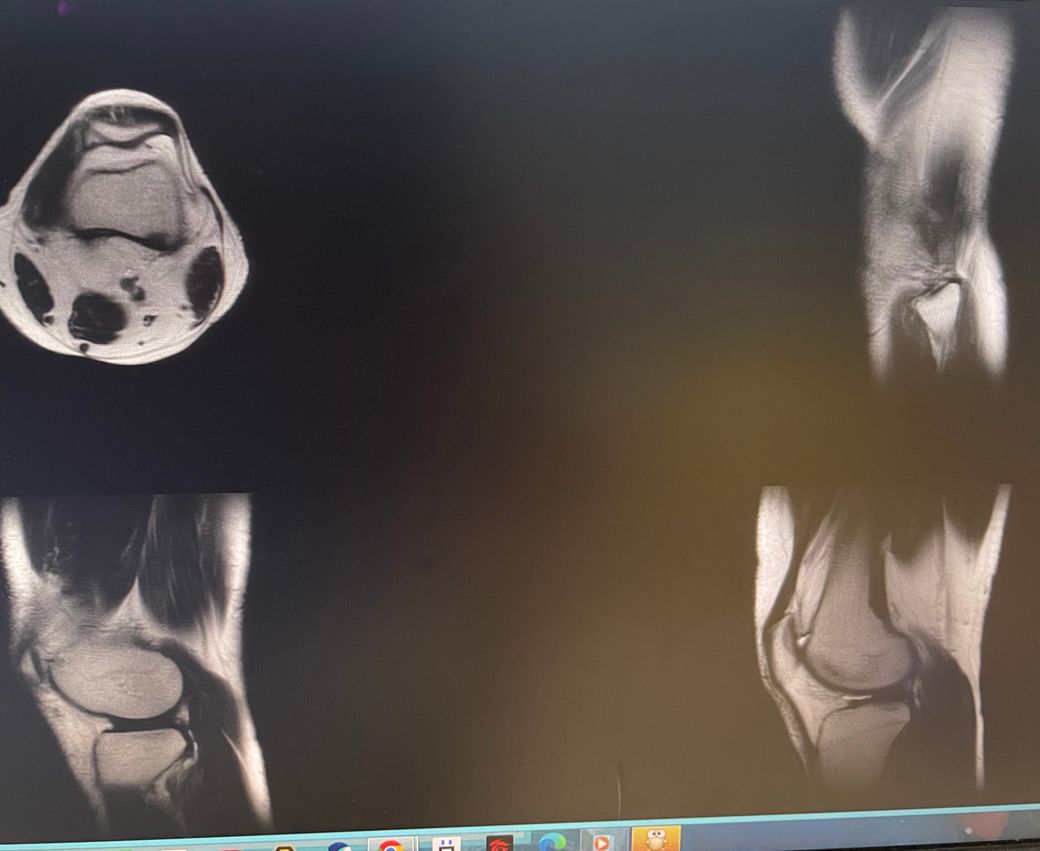

무릎 왼쪽 mri 사진 판독 부탁드리겠습니다.

안녕하세요 3달전쯤에 무릎을 다쳐서 약 한달전에 mri를 찍었습니다.

현재 판독상 인대나 반월연골 손상은 없는 것으로 판독지에 기재되어 있습니다. 임상적인 증상도 중요하니 담당의사와 상의하시고 신검시에 해당과 군의관 판정을 받으시는 것이 좋겠습니다.

십자인대에는 문제가 없지만 반월판의 문제가 있는 것으로 보입니다.

ACL 즉 전방 십자 인대에 불규칙한 소견은 있으나 Tear 즉 십자 인대가 파열되었다는

소견은 관찰되지 않는 상태이며 연골에 퇴행성 변화는 있는 것으로 보이나 이 역시 R/O

으로 확실하지 않음을 의미합니다. 결과적으로 십자 인대의 파열이 명확하지 않는 상태로

군대를 연기할 사유가 될지는 모르며 전방 십자 등 인대 손상의 경우는 명확하게 파열된

소견을 보이지 않는 경우, 군 입대에 문제가 되지는 않을 것으로 생각됩니다.